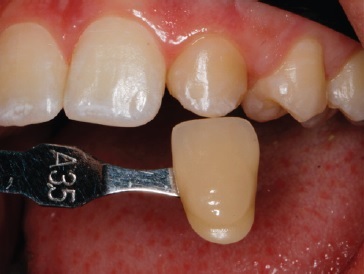

Before the final restorative phase, at-home dental bleaching was prescribed in a 2-hour daily regimen with 16% carbamide peroxide (VivaStyle 16%, Ivoclar Vivadent AG, Schaan, Liechtenstein). The effectiveness of dental bleaching (dental color change) was evaluated before and after the bleaching treatment in the upper and lower incisors, canines, and premolars using a visual method (Vitapan Classical Shade Guide; Vita Zahnfabrik, Bad Sackingen, Germany), with the results indicating a color improvement to A1.

Orthodontic treatment involving space closure was performed. After golden proportion (Figure 4) and Bolton’s anterior analysis, the presence of a 77.7% dental discrepancy in the anterior relation with mandibular excess was confirmed (14, 13, 11, 21, 23, 24, / 33, 32, 31, 41, 42, 43). Due to the agenesis of the maxillary lateral incisors and the need to perform esthetic restorations in the upper arch to improve smile harmony, a similar Bolton anterior discrepancy of 76% was obtained after restorations. After orthodontic treatment, shade selection was accomplished using a Vita Shade Guide (Figure 5), and dental bleaching was performed. Afterward, according to clinical findings and with careful consideration of all treatment options available for rehabilitation, it was decided that the maxillary canines and first premolars would be additively remodeled to the shape of lateral incisors and canines, respectively, using direct composite (Figure 6), which provides advantages in symmetrical cases.

A 19-year-old female patient presented with primarily esthetic concerns. An intraoral examination revealed a Class I right molar, a Class II left molar, and a deep bite (Figure 17). Orthodontic treatment was performed to obtain bilateral Class I molar and canine relationship and, in turn, improve the overbite and remove the traumatic occlusion responsible for the gingival recession on the left mandibular incisor. Bolton’s anterior analysis confirmed a dental discrepancy in the anterior sector to mandibular excess with a proportion of 83.1% (13, 12, 11, 21, 22, 23 / 43, 42, 41, 31, 32, 33). It was caused by the maxillary dental microdontia and the need to carry out esthetic restorations in the upper arch. A space was created on the distal surface of both microdontic lateral incisors to establish the Bolton’s proportion17 (Figure 18). After orthodontic treatment, shade selection was accomplished using a Vita Shade Guide (Figure 19), and dental bleaching was performed to optimize the harmony of the smile.